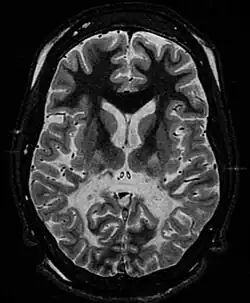

| White matter, with reduced volume and increased signal intensity. The anterior white matter is spared. Features are consistent with X-linked adrenoleukodystrophy. | |

The Loes score is a rating of the severity of abnormalities in the brain found on MRI. It ranges from 0 to 34, based on a point system derived from the location and extent of disease and the presence of atrophy in the brain, either localized to specific points or generally throughout the brain. A Loes score of 0.5 or less is classified as normal, while a Loes score of 14 or greater is considered severe. It was developed by neuroradiologist Daniel J. Loes MD and is an important tool in assessing disease progression and the effectiveness of therapy.[19]